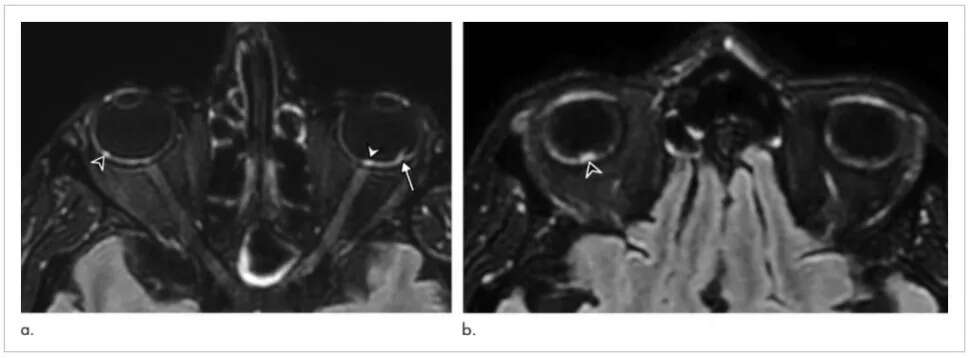

Okazało się, że dziewięć osób z tej grupy, czyli 7%, doświadczyło nieprawidłowości w funkcjonowaniu oczu. Obrazowanie wykazało bowiem obecność swego rodzaju guzków umiejscowionych z tyłu gałek ocznych. Takowe mogą być pozostałościami po zapaleniu bądź uszkodzeniu oczu.

Wspomniane guzki znajdowały się w obrębie plamki żółtej, która jest powiązana ze zdolnością do ostrego widzenia obiektów znajdujących się na wprost. 8 z 9 osób posiadało je w obojgu oczu. Autorzy badania zwracają uwagę na fakt, że problemy ze wzrokiem mogą ujść uwadze lekarzy zajmujących się ciężko chorymi pacjentami, w przypadku których priorytetem jest ratowanie życia.

COVID-19 była wcześniej wiązana z objawami dotyczącymi oczu, m.in. zapaleniem spojówek oraz uszkodzeniem siatkówki oka. W tym przypadku nie wiadomo, co doprowadziło do powstania guzków, choć jedna z hipotez zakłada, iż pojawiły się one na skutek zatkania naczyń krwionośnych.